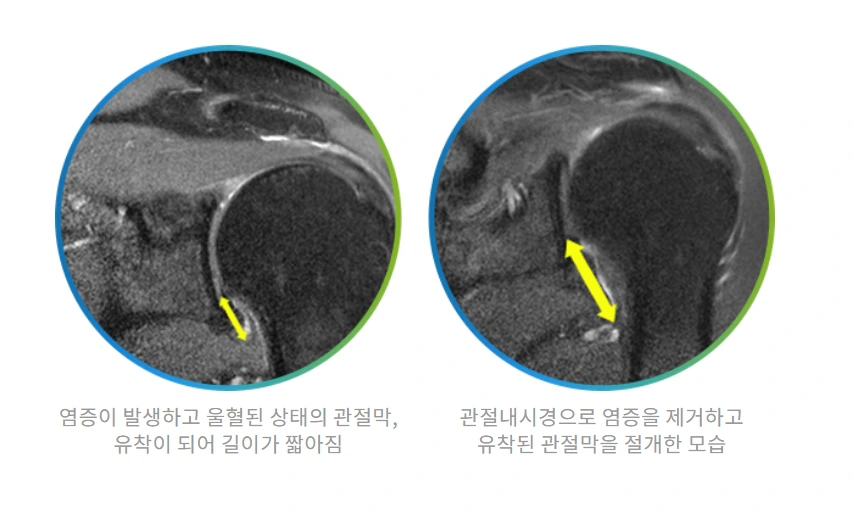

오십견수술치료.PNG

비수술적 치료에도 오십견이 호전되지 않거나 재발이 반복되면 관절내시경을 이용해 통증의 원인인 염증을 제거하고 유착된 관절막을 절개하는 수술을 진행합니다.